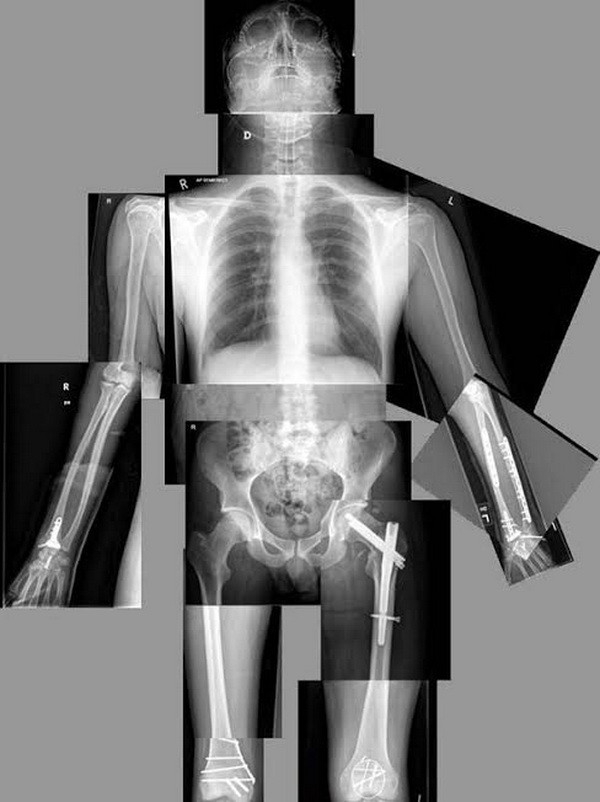

Cú ngã đó đã khiến tất cả các xương mặt của anh đã bị vỡ do hấp thụ xung lực để bảo vệ bộ não, đồng thời xương tứ chi của anh đều bị gãy. Sau một thời gian, Jon đã được đưa trở lại Anh để thực hiện phẫu thuật chỉnh hình tái tạo tại bệnh viện Nữ hoàng (QMC) ở Nottingham.

Các bác sỹ phẫu thuật đã tạo ra một mô hình mô phỏng hộp sọ của Fenton, sử dụng một máy in 3D, nhằm thực hiện phẫu thuật thử nghiệm. Sau ca phẫu thuật khó nhọc kéo dài 14 tiếng đồng hồ, các bác sỹ đã phá vỡ và tái thiết lập lại gần như tất cả các xương trên gương mặt Fenton.

Phẫu thuật tái tạo hộp sọ bệnh nhân bằng công nghệ in 3D ảnh 2Các bác sỹ tái tạo hộp sọ của Jon bằng công nghệ in 3D. (Nguồn: express.co.uk)